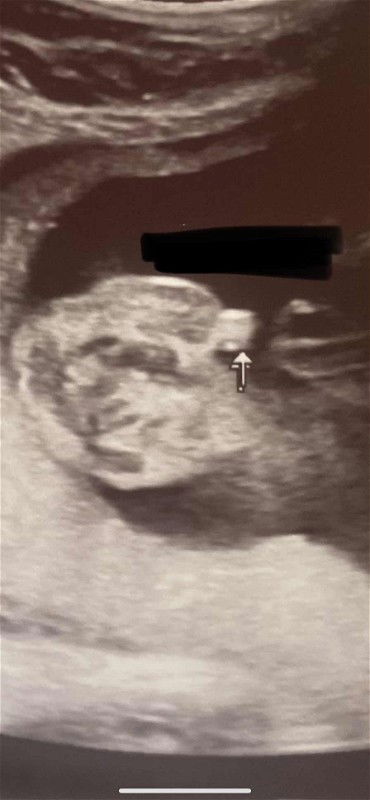

Gender check ultrasound

Mga mi pwede mag ask, pa confirm po kung boy or girl. Salamat po sa makaksagot. And edd ko po ay july 11